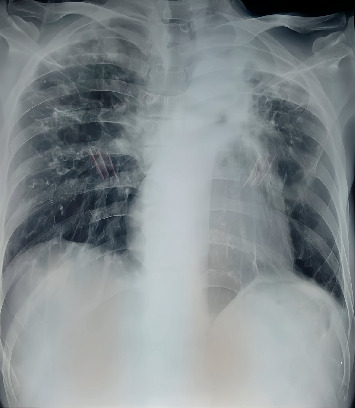

Multidrug-resistant tuberculosis (MDR-TB) is characterized by resistance to at least isoniazid and rifampicin. Linezolid is an antibiotic used for drug-resistant Gram-positive bacteria and is a treatment option for MDR-TB. However, its use is associated with optic neuropathy, presenting as acute worsening and bilateral vision loss, typically within 4 months of therapy. A 47-year-old male with MDR-TB relapsed during the sixth month of an individualized treatment regimen at Dr. Soetomo General Academic Hospital, Surabaya. The patient presented with weakness and anemia, receiving a regimen including levofloxacin (750 mg), linezolid (600 mg), clofazimine (100 mg), and cycloserine (500 mg). In the ninth month, the patient developed visual disturbances, initially suspected to be caused by an intracranial tumor. Despite various examinations and treatments, there was no improvement until linezolid was discontinued. The patient's visual complaints gradually improved following the cessation of linezolid therapy. This case underscores the potential for linezolid to cause optic neuropathy during prolonged treatment for MDR-TB. Detailed ophthalmologic examinations, including optical coherence tomography (OCT) and magnetic resonance imaging (MRI), confirmed optic neuropathy without intracranial pathology. Despite high-dose steroid therapy, the patient's vision improved only after 1 month since discontinuing linezolid. This highlights the importance of monitoring for ocular toxicity in patients undergoing long-term linezolid therapy and suggests that timely intervention can prevent permanent visual impairment. The case demonstrates the reversible nature of linezolid-induced optic neuropathy upon drug cessation and emphasizes the need for regular ophthalmologic assessments in patients receiving prolonged linezolid treatment. This report contributes to the understanding of the adverse effects of linezolid and underscores the importance of vigilant monitoring and alternative therapeutic strategies for MDR-TB.